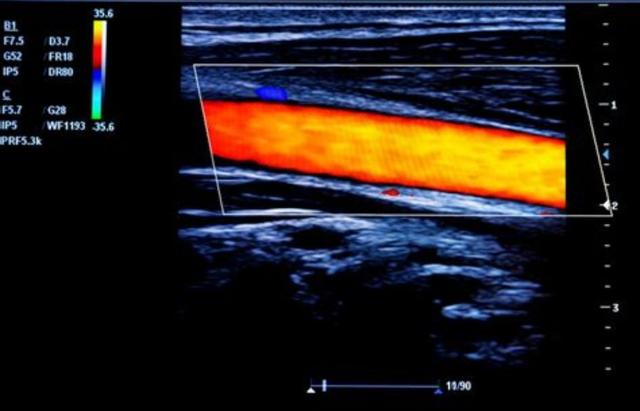

●下肢の血管の問題.エストロゲン自体が血管の透過性を低下させ、血清コレステロールを低下させる役割を持つため、年齢的な要因も相まって、下肢の血液供給に問題がある可能性は否定できない。下肢の血管超音波検査重症の場合は、下肢の血管にプラークや狭窄があるかどうかを調べるために、以下の検査を行う必要がある。下肢血管造影下肢血管系全体のさらなる解明が必要である。